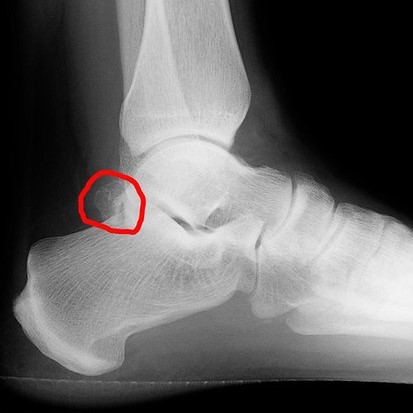

Σύνδρομο Os Trigonum Ο πόνος στο πίσω μέρος του αστραγάλου είναι ένα συχνό σύμπτωμα σε αθλητές, χορευτές αλλά και σε άτομα που καταπονούν συστηματικά τα πόδια τους. Μία από τις λιγότερο γνωστές αλλά σημαντικές αιτίες είναι το Σύνδρομο Os Trigonum. Ας δούμε αναλυτικά τι είναι και πώς αντιμετωπίζεται. Τι είναι το Os Trigonum; Το os…